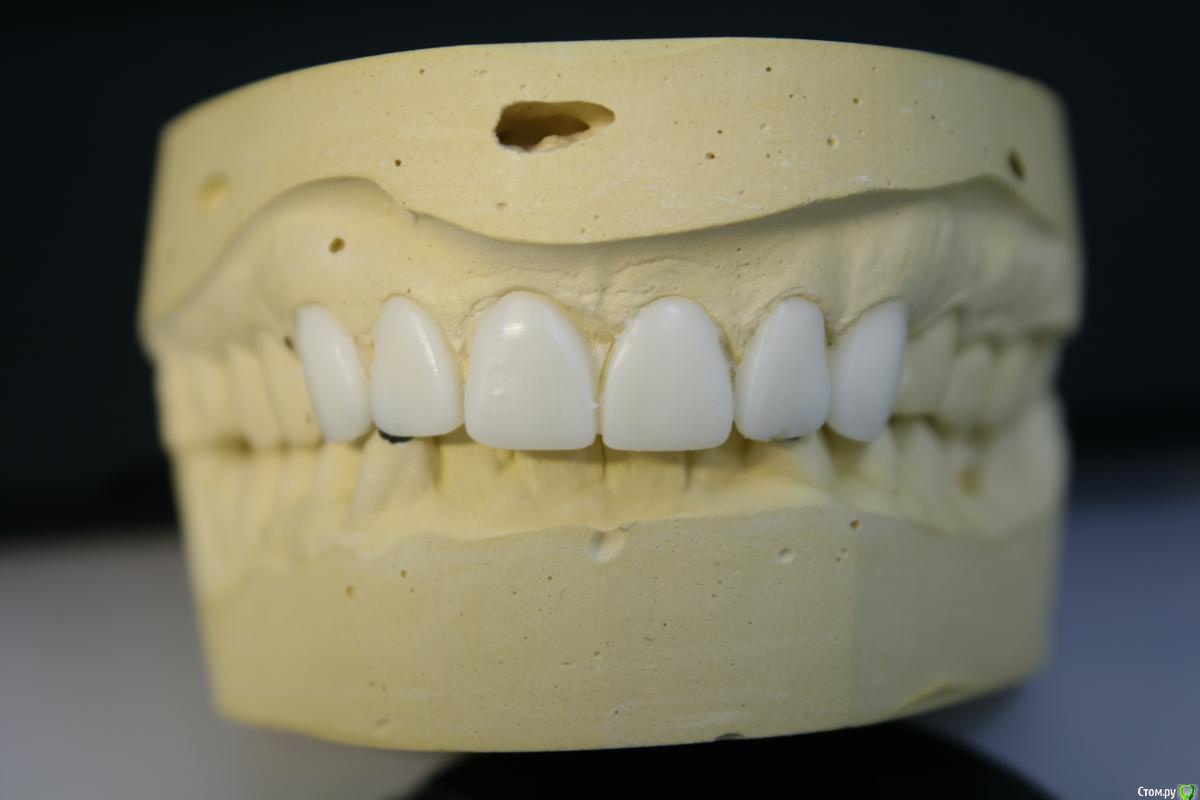

kramer Опубликовано 22 января, 2018 Автор Поделиться Опубликовано 22 января, 2018 Я не пойму,почему все в один голос твердят,что здесь нужно поднимать прикус?Какие показания? С чего вы это решили?Нужно исходить из возраста пациента. Да здесь видны фасетки стираемости,но не стоит забывать,что есть еще компенсация стираемости в виде роста альвеолярного отростка с зубами (гипертрофия) и далеко не всегда стираемость приводит к снижению МАВ. Здесь как раз намного важнее определиться с ЦС и ВНЧС,как минимум провести тесты,сделать КТ сустава.Если все в норме,то нет нужны поднимать высоту. Я думаю в данной клинической ситуации возможно отмоделировать достточно неплохо фронт,хотелось бы увидеть ваш вариант воска. Вот воск. С нижних клыков убрано по 1-1,5 мм примерно Ссылка на комментарий

StomV Опубликовано 22 января, 2018 Поделиться Опубликовано 22 января, 2018 Вот воск. С нижних клыков убрано по 1-1,5 мм примерноВ целом,я думаю нормально,но чем продиктована длина зубов? Если хотите увеличить длину,ведь ее можно увеличить за счет небольшой коррекции десневого края,а не за счет удлинения зубов.Опять же не понятна линия улыбки пациента. И не совсем понятна линия горизонта. Попробуйте сделать мокап в орту и посмотреть,что получится. Ссылка на комментарий

kramer Опубликовано 23 января, 2018 Автор Поделиться Опубликовано 23 января, 2018 В целом,я думаю нормально,но чем продиктована длина зубов? Если хотите увеличить длину,ведь ее можно увеличить за счет небольшой коррекции десневого края,а не за счет удлинения зубов.Опять же не понятна линия улыбки пациента. И не совсем понятна линия горизонта. Попробуйте сделать мокап в орту и посмотреть,что получится.Я не могу сделать такой мокап без спиливания клыков. Дело не только в длине, а ещё в развернутых двойках. Если их выравнивать коронками, не хватает места. Либо я че то не понимаю Ссылка на комментарий